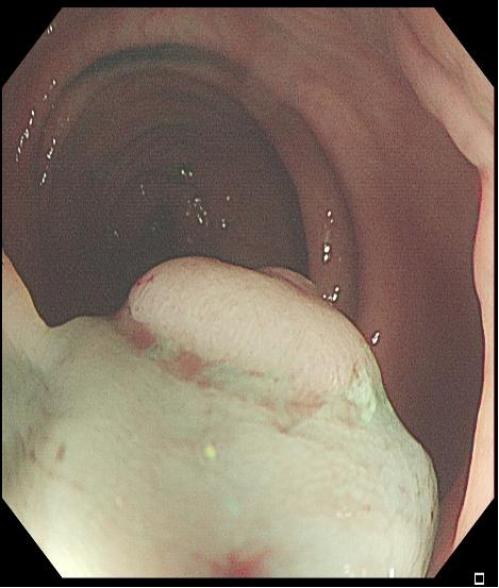

适用于不同大小隆起型病变Ⅰp型、Ⅰsp 型以及小型(<2 cm)Ⅰs型(具体分型标准可参照)病变的切除。小型Ⅰp型病变,圈套切除相对简单,可采用冷或热圈套切除,切除时应在保证完整切除病变同时,保留一定长度的蒂部或与肠壁保持一定距离,收紧圈套后,应抖动圈套器,观察有无周围正常肠黏膜一并套入,防止损伤肠壁。

上下滑动查看△

图2 小型Ⅰsp 型病变热圈套切除示意图